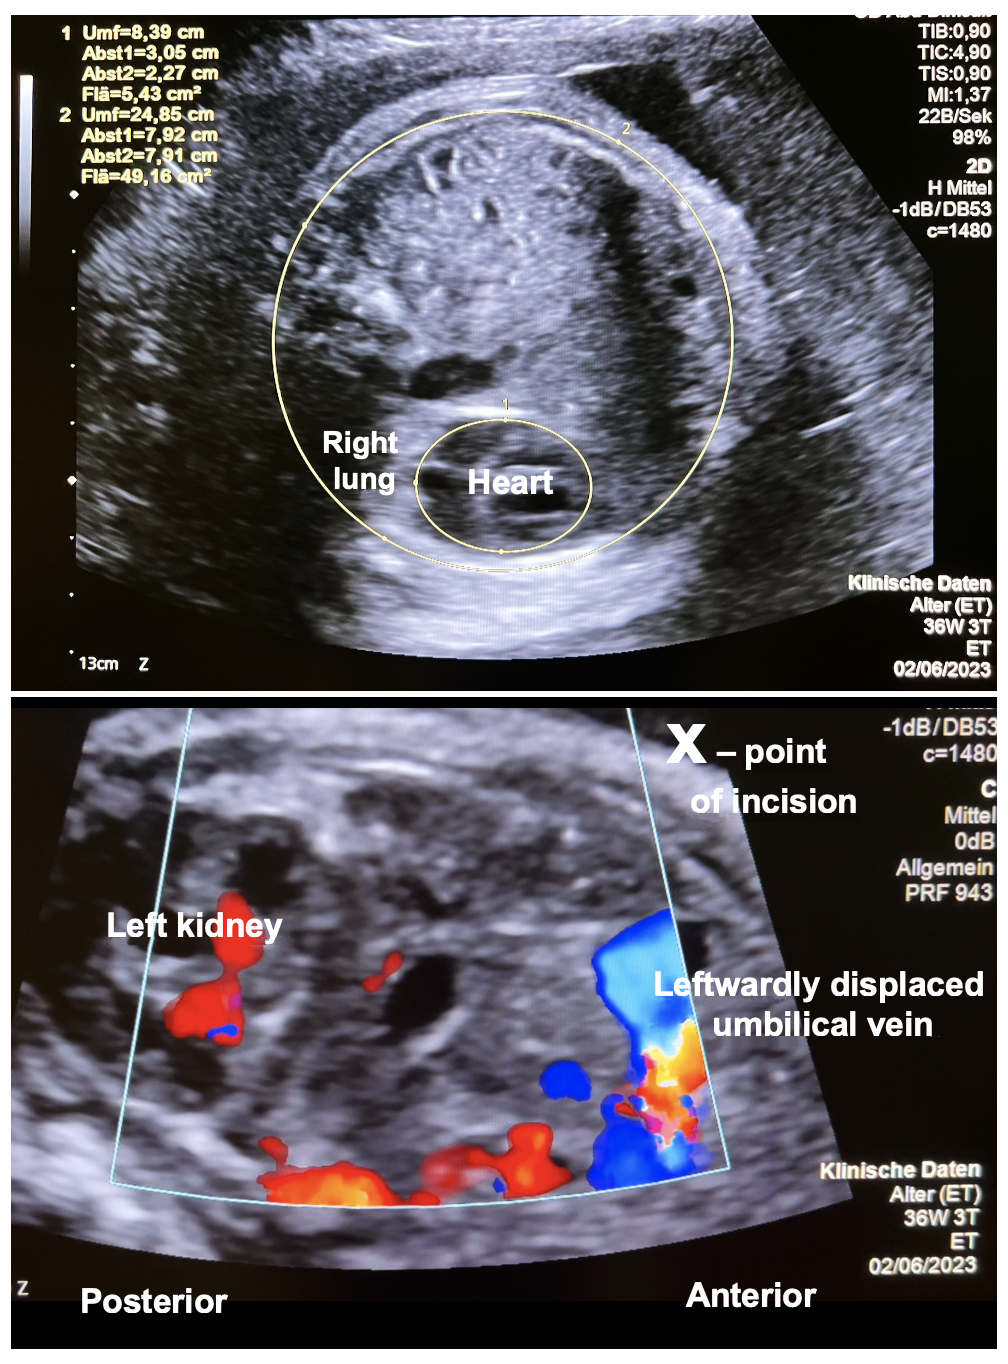

Case Report: Fetoscopic Laparoschisis (FETO-LAP)—A New Therapeutic Route to Explore for Fetuses with Severe Diaphragmatic Hernias

Case